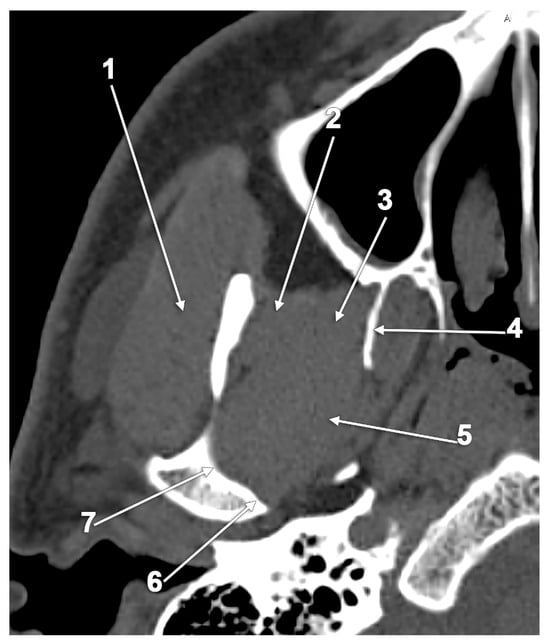

5.1. Broad Lateral Pterygoid Plates

5.2. The Pterygospinous and Pterygoalar Bars

6. Aberrant Insertion Sites and Accessory Bundles of the Lateral Pterygoid Muscle

6.1. The Extraincisural Insertion of the Lateral Pterygoid Muscle

The Accessory Pterygoid Fovea